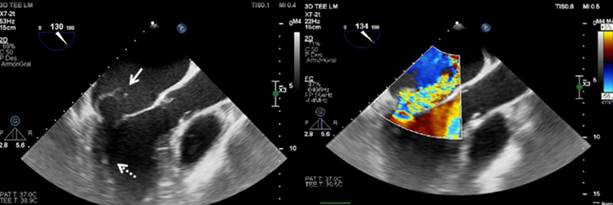

Se realiza un ecocardiograma transtorácico en el que se observan cavidades izquierdas dilatadas, función sistólica conservada con FEVI de 65% y una imagen sugestiva de vegetación a nivel de válvula mitral que presentaba insuficiencia severa. Posteriormente, se realiza un ecocardiograma transesofágico (figura 2) que evidenció una válvula mitral con anillo de 47 mm donde se observaba flail a nivel de festones P2 y P3 con rotura cordal e insuficiencia severa y una masa de 10 mm × 7 mm, algodonosa, móvil, adherida al aparato cordal del músculo posterolateral. Con estos hallazgos, se inicia tratamiento antibiótico por vía parenteral con base en cefazolina.

Figura 2: A. Ecocardiograma transesofágico a nivel de esófago medio. El eje largo del tracto de salida del ventrículo izquierdo está dilatado. La flecha continua indica flail de la valva menor de la válvula mitral. Se puede apreciar pequeña vegetación a nivel del aparato subvalvular (flecha punteada). B. Doppler color en el que se observa un jet de insuficiencia mitral severa excéntrica que ocupa gran parte de la aurícula izquierda que se encuentra dilatada.